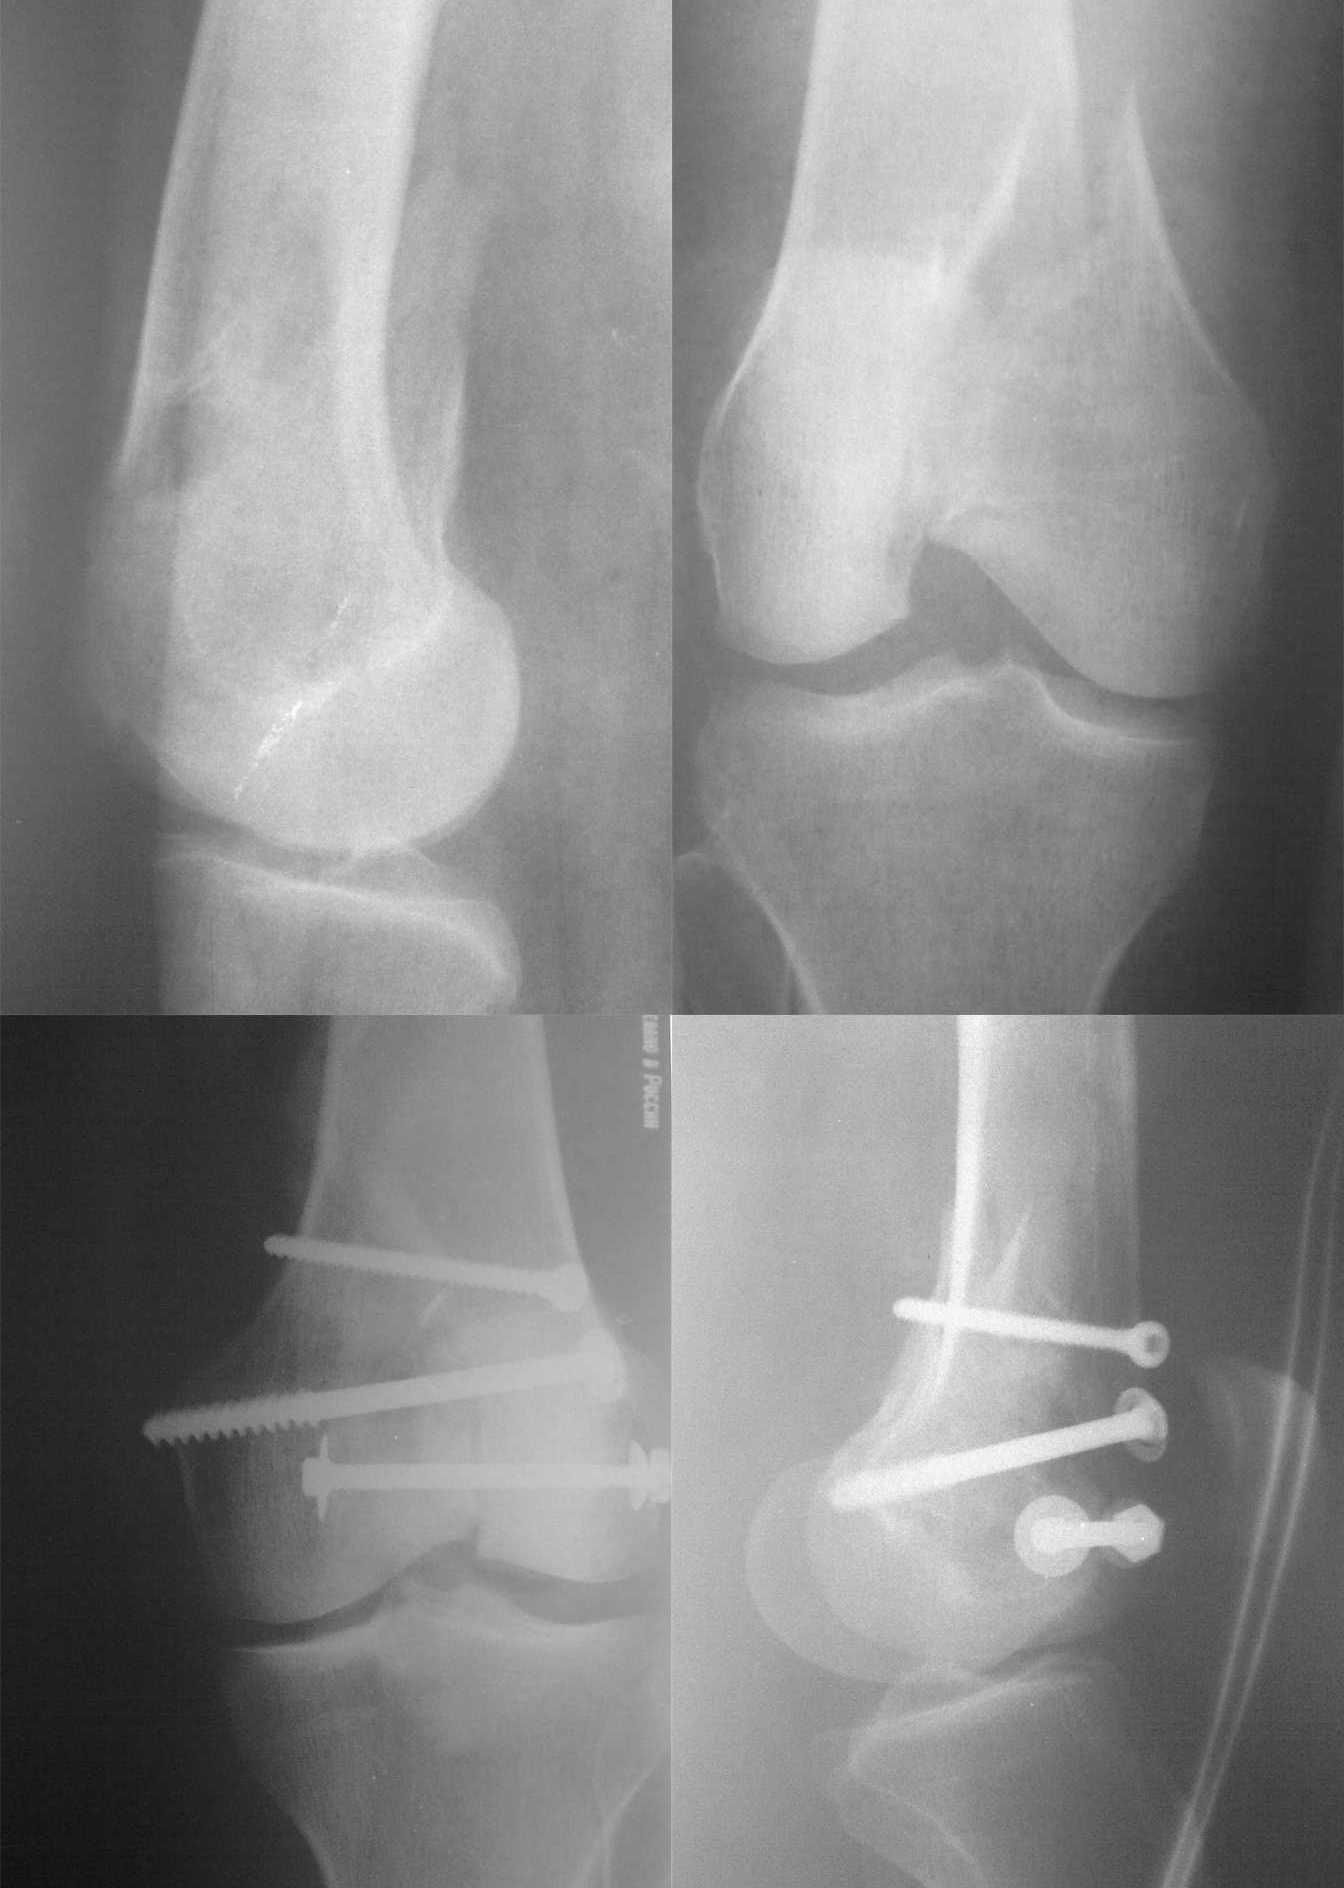

синтез мыщелка бедра

по поводу остеосинтеза свежего перелома внутреннего мыщелка бедра

Hi! This is familar misstake. Fixation I think was done percutaneus or mini invasive. Fracture not redused. One of the component this fracture - sagital. This is Goffa like frctures

Reduction this fracture more beter to do with arthroscopic control or arthrotomy. Good lack in feuther cases

Dear Michael, first of all I agree with you √ unfortunately this reduction is not perfect enough. In addition, after precise reduction and screw fixation fractures like this need buttressing plating as a rule. I think this patient is young, because bone looks good enough, therefore, reoperation can be good desigion here. However, unlike of your opinion I rather think that it was open (not percutaneus) reduction┘

Если вопрос заключается в качестве сопоставления; моё мнение, что при наличии таких крупных отломков суставная поверхность должна сопоставляться более тщательно, тем более при свежем переломе.

Мыщелок отрепонирован не совсем конгруэнтно.

Считаю такой остеосинтез не достаточно жесткий, наверняка в послеоперационном периоде наложена иммобилизация.

По рентгенограмме похоже имеется перелом мыщелка большеберцовой кости без смещения, уменьшение высоты суставной поверхности между поврежденными мыщелками -- в пользу повреждения мениска, который наверное не был удален во время остеосинтеза.

Нужно было провести ЯМР для оценки состояния крестообразных и боковых связок и менисков, затем остеосинтез DCS, и шов или экономная резекция мениска(если есть повреждение), а после консолидации и реабилитации перелома, восстановление ПКС или ЗКС если имеется повреждение.

Ваш больной нуждается в реостеосинтезе, потому что:

- дополнительная к остеосинтезу гипсовая иммобилизация препятствие для реабилитации,

- нижний шуруп с шайбами может создать феморо-пателярный конфликт,

- наружно-боковой конец последнего шурупа создать конфликт с "tractus iliotibialis" по типу синдрома автомобильного дворника.

А.А.! Мыщелок срастется с удлинением, следовательно - вальгусное колено со всеми вытекающими. При таком синтезе однажды имел асептический некроз мыщелка с большими проблемами - с трудом удалось избежать судебных дел, спасла Г.С. Обязательно была нужна пластина (L-образная на худой конец) - вели бы больного без гипса с разгрузкой ноги костылями. Артротомия была?

Добрый вечер, коллеги! IMHO либо переделать, либо кропотливо реабилитировать(а получится?)т.к. сохраняется и сагиттальное и вертикальное смещение. Компенсаторные возможности организма ,конечно великие,но не беспредельные

Согласен смнением, что суставные поверхности не конгруентны и фиксация не достаточно жесткая. О внутресуставных повреждениях можно говорить всё что угодно. Необходимо переделывать операцию. Если не возможна артроскопическая ассистенция то необходимо выполнить хотя бы миниартротомию для контроля репозиции и оценки внутрисуставных структур.